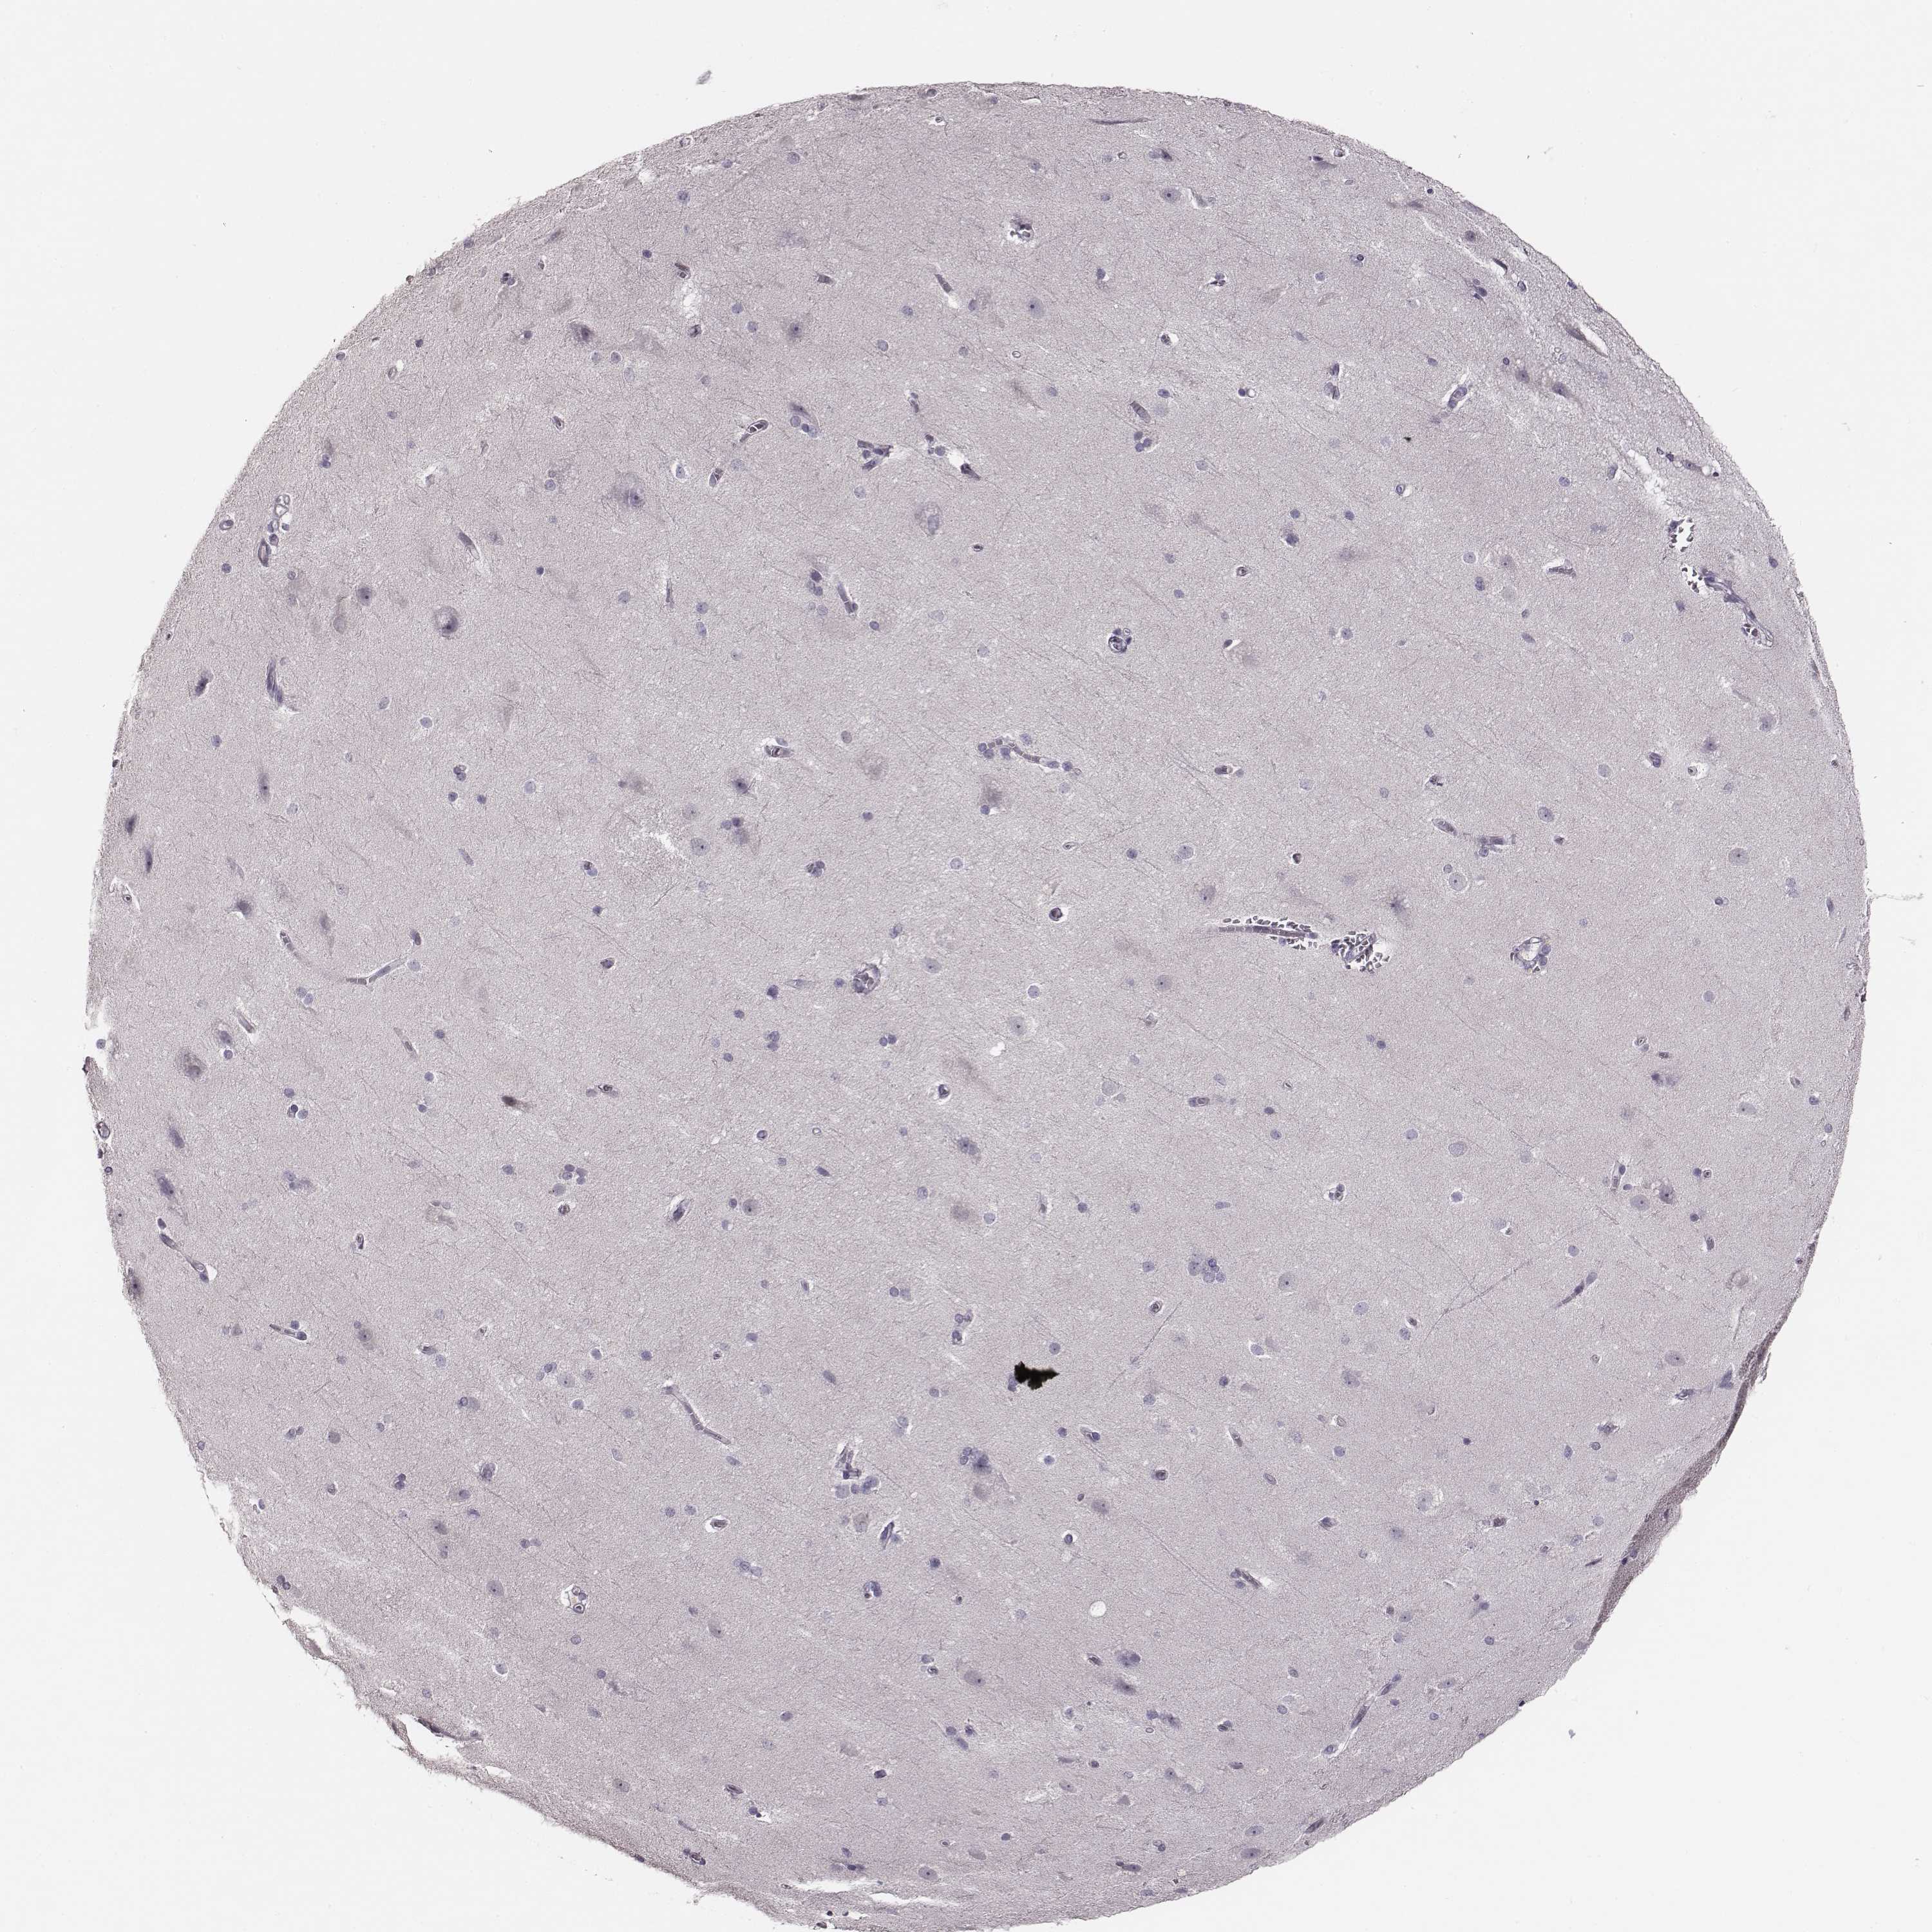

KAAG1